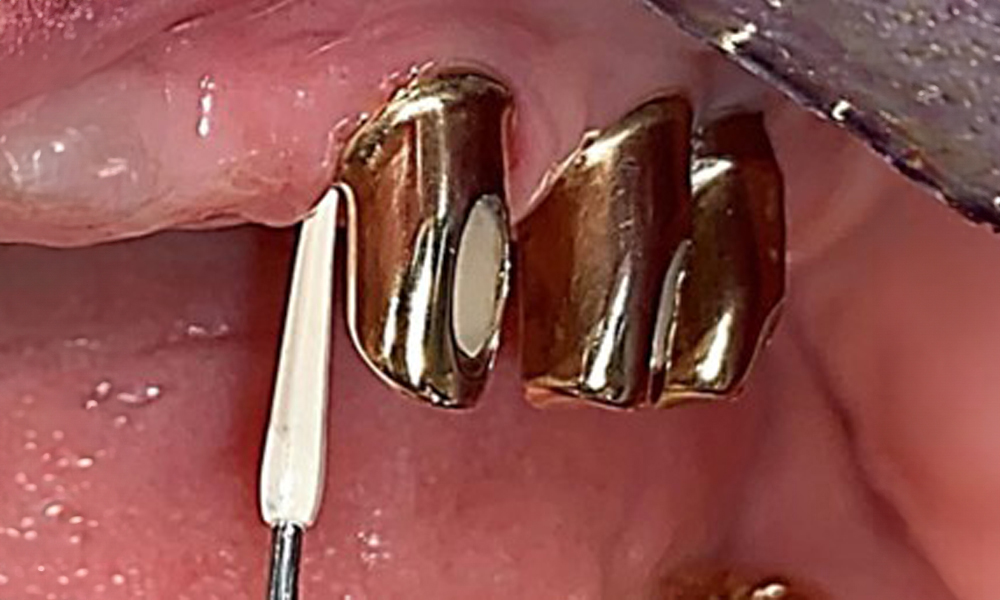

The periodontal condition remains stable. There was no gingival or peri-implant soft tissue inflammation. At 1 to 3 mm, the probing depths were within the physiological range. There are generalised recessions measuring 1 to 3 mm. Implant 23 has an increased probing depth of 4 mm, although there are no signs of secretion or bleeding (Fig. 6). The total BOP is 12%.

Based on the medical history, the risk of complications is classified as mild to moderate due to the intake of ASA 100 and bisoprolol. It should be noted that increased bleeding may occur during treatment, particularly if gingivitis is present. The risk is classified as low in the present case, as the patient maintains excellent intraoral hygiene. Due to the otherwise stable intraoral status over many years, the needs determined during the intraoral examination will be decisive for her treatment. The findings observed during any dental appointment will determine the subsequent course of treatment. Determination of bleeding status is mandatory to detect gingival changes in peri-implant tissues (Fig. 6).

Probing implant 23 at a probing depth of 4 mm using a plastic probe, showing negative BOP findings and a hyperplastic papilla.

Fig. 6: Probing implant 23 at a probing depth of 4 mm using a plastic probe, showing negative BOP findings and a hyperplastic papilla.

The periodontal status should be thoroughly examined once a year. This examination provides comprehensive documentation of the periodontal and implant findings, including pocket depths, periodontal recession and furcation involvement. This will ensure a rapid response to any potential progression of the mucositis, gingivitis, periodontitis or peri-implantitis. Implant probing using a plastic probe is recommended. In the present case, a mesial probing depth of 4 mm was detected mesial to implant 23. No suppuration or bleeding was detected, indicating the absence of peri-implantitis.